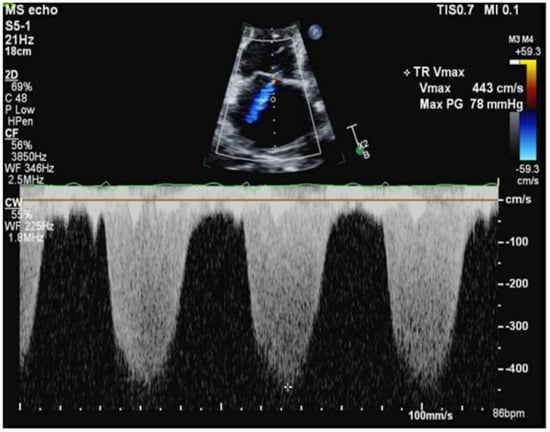

Transthoracic echocardiography (TTE) demonstrated preserved left ventricular function (62%), but severe right ventricular dilation with decreased function, severe tricuspid regurgitation, and significant PH (Figure 4). A ventilation/perfusion scan revealed a low probability for PE, and pulmonary function tests indicated a moderately severe restrictive ventilatory defect. Left heart catheterization revealed non-obstructive coronary artery disease. The right heart catheterization (RHC) results were indicative of precapillary PH, showing pulmonary artery pressures of 88/37/54 mmHg, a pulmonary capillary wedge pressure (PCWP) of 6 mmHg, a pulmonary vascular resistance (PVR) of 15 Wood Units (WU), and a cardiac index (CI) of 2.0 L/min/m2.

Figure 4. Continuous wave doppler showing severe pulmonary hypertension.